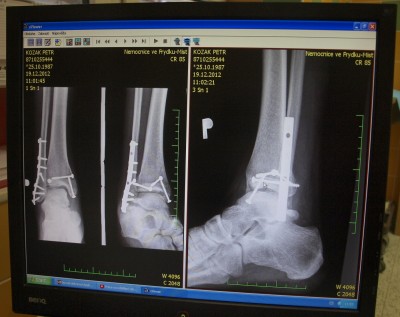

Petis píše:Takže situace je taková, že veškeré práce, které byly v plánu přes zimu se musí odložit na neurčito. Důvod je mnohonásobná zlomenina kotníku + přetrhané všechny vazy. Takže mám v pravém kotníku x šroubů + nějakou výztuž. Léčba odhadem na 4-5 měsíců. Honda je momentálně zazimována na baráku u rodičů. ...tak to dopadá když se někdo rozhodne, že bude přes zimu sportovat :D

Nahoď foto potom nech sa pobavíme (môj členok 2009)...

Vypadá to asi nějak takhle, ale prý se to hojí víc než dobře, tak snad budu co nejdřív normálně chodit.